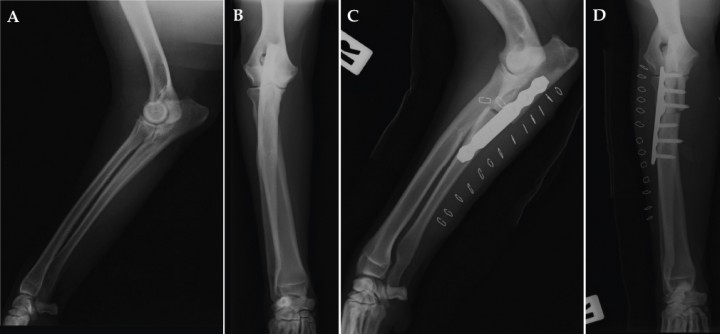

Este es un estudio clínico retrospectivo en el que se incluyen perros diagnosticados de ECM de codo mediante evaluación clínica, estudio radiográfico (Fig. 1), tomografía computarizada (Fig. 2) y evaluación artroscópica (Fig. 3). Dichos pacientes fueron intervenidos mediante la técnica quirúrgica PAUL (Fig. 4) tras la realización de una artroscopia de codo en el mismo acto quirúrgico. Los criterios de inclusión fueron los siguientes: perros que habían sido sometidos a dicho procedimiento quirúrgico en uno o ambos codos y que habían superado un periodo de evolución de cómo mínimo 4 meses. En el caso de intervenirse ambos codos, estas intervenciones debían haberse hecho en dos actos quirúrgicos independientes y con un intervalo mínimo entre ellos de 4 meses.

<p>Radiografía lateral (A) y cráneo-caudal (B) prequirúrgicas de un codo afectado de enfermedad del compartimento medial. Radiografía lateral (C) y cráneo-caudal (D) postquirúrgicas inmediatas; se aprecia la osteotomía y la colocación de la placa correctamente, observándose el desplazamiento del fragmento proximal producido por el implante.</p>

Figura 1

Radiografía lateral (A) y cráneo-caudal (B) prequirúrgicas de un codo afectado de enfermedad del compartimento medial. Radiografía lateral (C) y cráneo-caudal (D) postquirúrgicas inmediatas; se aprecia la osteotomía y la colocación de la placa correctamente, observándose el desplazamiento del fragmento proximal producido por el implante.

En primer lugar, mediante la artroscopia se realizaba el examen completo de la articulación: incisura cubital, cabeza del radio, cóndilos lateral y medial y coronoides lateral y medial (Fig. 3). En los casos en que existía un fragmento de coronoides medial, aislado o no, éste era extraído durante el procedimiento artroscópico. En las superficies en que se apreciaba condromalacia severa, erosiones o úlceras cartilaginosas (principalmente en coronoides medial), dichas zonas eran legradas y cureteadas hasta la aparición de zona de hueso subcondral sano, que se evidenciaba por la presencia de sangrado del mismo. Tras estudiar los signos de estrés en el compartimento medial (realizando los procedimientos necesarios y previamente expuestos vía artroscópica) y comprobar la integridad del compartimento lateral, se continuaba con la realización de la técnica quirúrgica PAUL. Para ello se realizaba un abordaje caudolateral al tercio proximal de la diáfisis cubital, para posteriormente realizar una osteotomía cubital y colocar una placa de sistema avanzado de bloqueo (ALPS, Kyon, Zurich) de 2 o 3 mm de escalón según las mediciones realizadas (Fig. 4). La medición se realizaba sobre la proyección radiológica cráneo-caudal, valorando el ángulo que formaba el eje longitudinal del radio con el eje de la articulación del codo. Según especifica el fabricante, si este ángulo es mayor de 82º se emplea un escalón de 2 mm y si es menor, de 3 mm.